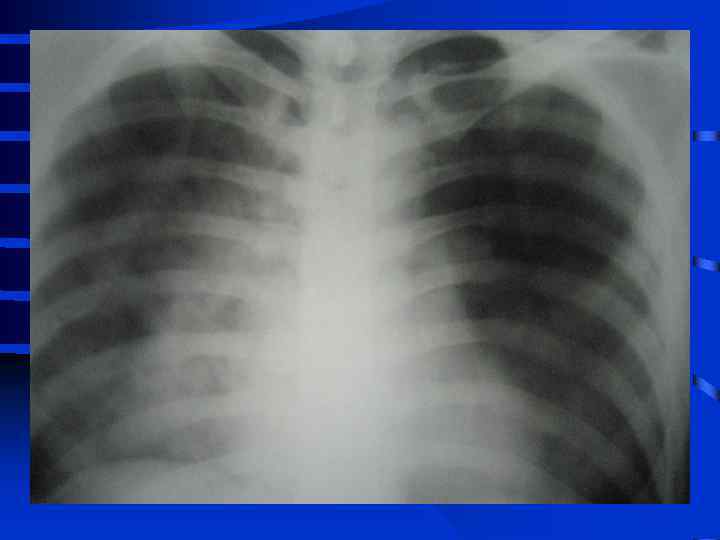

• I стадия Все изменения носят умеренный характер, индекс оксигенации (Pa. O 2/Fi. O 2) более 300, Pa. CO 2 снижен до 34 - 32 мм. рт. ст. , рентгенографически полнокровие легких, ячеистая деформация на фоне усиленного легочного рисунка. • II стадия Повторное, часто резкое ухудшение состояния. Психические нарушения (беспокойство, неадекватность), тахикардия свыше 110 - 120 в мин. , АД сист. более 150 мм. рт. ст. , индекс оксигенации менее 250 - 200, артериальная гипокапния. Рентгенографически - появление мелкоочаговых теней на периферии